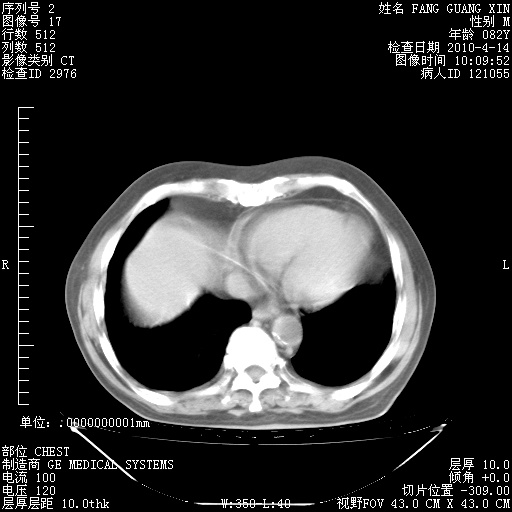

4月14日肺部CT

楼主| 发表于 2010-4-28 16:51 | 显示全部楼层

楼主| 发表于 2010-4-28 16:53 | 显示全部楼层

肺部CT平扫未见异常。